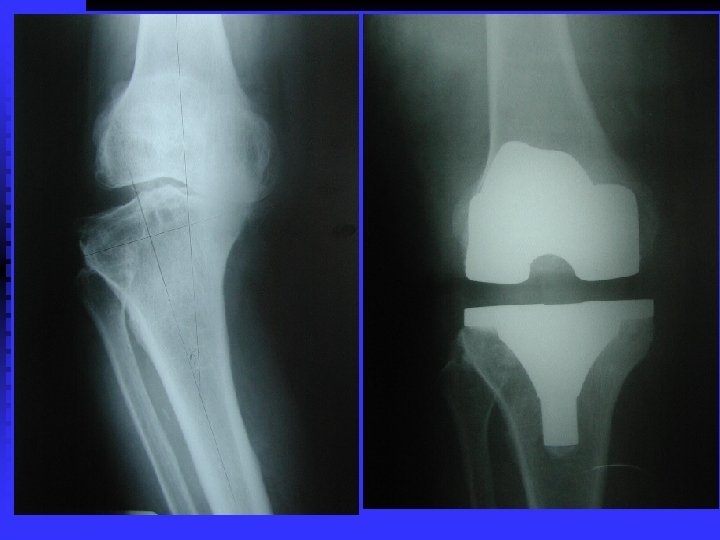

OA RÖNTGEN BULGULARI n Eklem aralığında daralma (kıkırdak incelmiş) n Eklem aralığının kalmaması (kıkırdak bitmiş) n Yük binen yerlerde kistler n Yük binmeyen yerlerde osteofitler

CERRAHİ TEDAVİ Artrodez (eklemin dondurulması) n Osteotomi (aks veya eklem uyumu düzeltilir) n Debridman (artroskopik temizleme) n Artroplasti n • • Parsiyel veya total protez Rezeksiyon (kısa ve fonksiyonu kötü ekstremite)